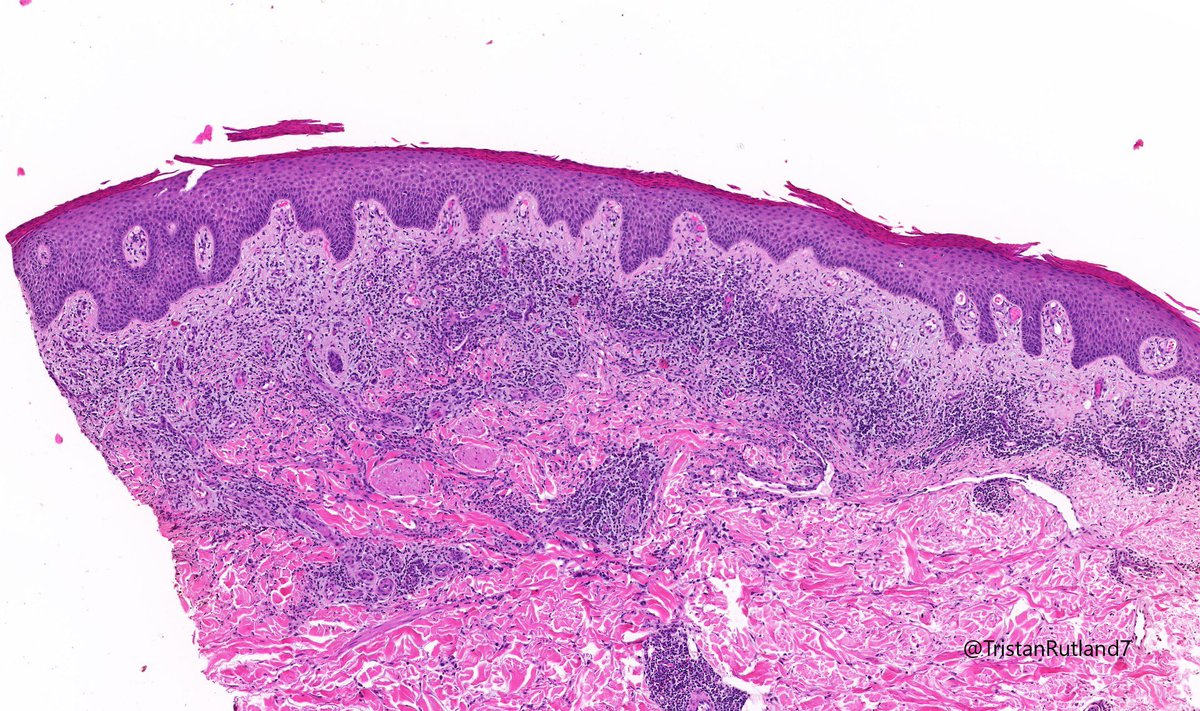

Female, adult, leg.

Large cell transformation of mycosis fungoides (MF).

3/ Large cell transformation is defined by greater than 25% large cells (4X size normal lymphocytes) or nodular aggregates in dermis.

4/ It usually arises from tumour stage (rare cases arising from patch stage have occurred).